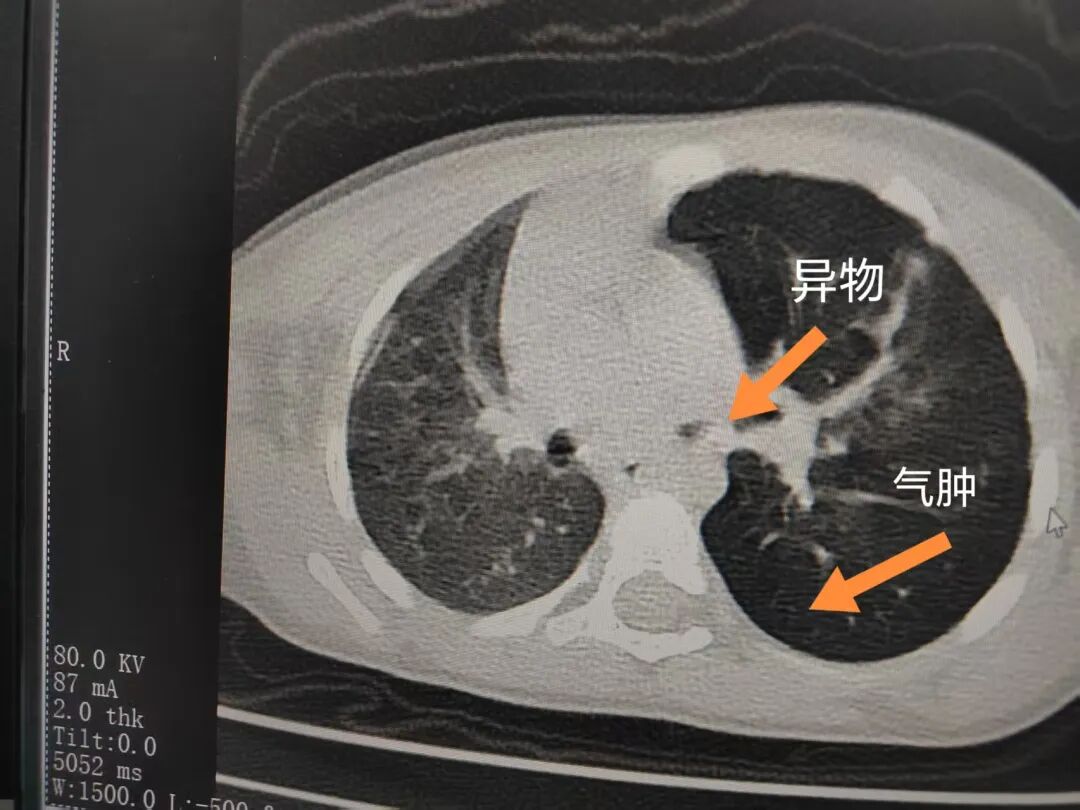

三天后(11月13日),趙寶出現(xiàn)高熱、咳喘加重,家長著急了,再次帶他來到醫(yī)院。CT檢查顯示左肺過度充氣,左肺上下葉支氣管主干見不規(guī)則高密度影,左肺上葉可見大片狀密度增高影,縱隔窗實(shí)變,提示為“左側(cè)支氣管內(nèi)異物并繼發(fā)性改變,左肺上葉舌段肺膨脹不全”。

市二院小兒呼吸內(nèi)科團(tuán)隊(duì)迅速為患兒制定了周密的手術(shù)方案,并很快安排了氣管鏡探查。術(shù)中,主治醫(yī)師田慧等憑借嫻熟的氣管鏡操作技術(shù)成功將異物大塊板栗取出。由于板栗在氣管內(nèi)存留時(shí)間較長,質(zhì)地軟糯易碎,大大增加了手術(shù)難度。檢查還發(fā)現(xiàn),異物停留部位的氣管黏膜已出現(xiàn)充血紅腫、糜爛,導(dǎo)致患兒住院時(shí)間相應(yīng)延長。此次事件給趙寶的家庭帶來了不小的驚嚇與擔(dān)憂,也再次為廣大家長敲響了警鐘。

市二院小兒呼吸內(nèi)科副主任楊亞娟介紹,異物誤入氣道可能導(dǎo)致氣道阻塞,嚴(yán)重時(shí)可引發(fā)窒息,甚至危及生命。若異物進(jìn)入支氣管,造成不完全堵塞,可引起阻塞性肺氣腫;如完全堵塞支氣管,則可能導(dǎo)致肺組織萎縮,形成肺不張。此外,若異物存留時(shí)間較長,或?yàn)橹参镄援愇铮菀缀喜⒓?xì)菌感染,產(chǎn)生膿性分泌物,進(jìn)而發(fā)展為肺炎。她強(qiáng)調(diào),盡早診斷并取出異物,是減少并發(fā)癥、降低病死率的關(guān)鍵。